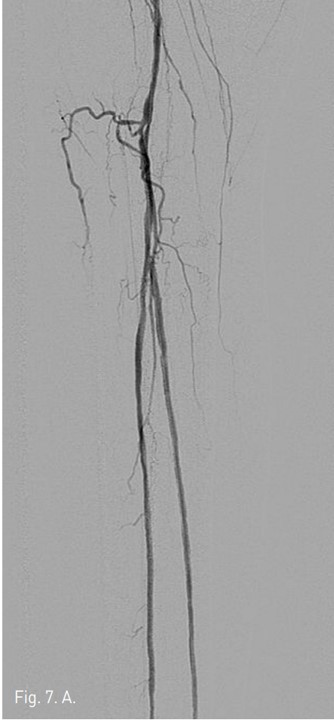

Fig. 7. A

Fig. 7. Final angiography shows complete recanalization of arterial flow in both left posterior and left peroneal arteries.

Fig. 7. B

우총대퇴동맥을 통해서 5Fr catheter 내로 goose neck snare를 insertion하여 GT Guide wire를 잡아빼낸 후(Fig. 5A), 이를 다시 SV 5 Guide wire (Cordis, Miami, USA)로 교환하였다 (Fig, 5B). 3mm/10cm balloon을 우총대퇴동맥에서부터 삽입하여 우측 후경골동맥에 대해 subintimal angioplasty를 시행하였고 (Fig. 6), final arteriogram 상 우측 비골동맥과 우측 후경골동맥의 혈류는 완전 재개통되었다 (Fig. 7A 7B). 우측 SFA 협착 부위에 대해서 6mm/12cm SMART stent를 삽입한 후 시술을 마쳤다. 일주일 뒤 시행한 doppler 검사는 시술 이전과 크게 차이가 나지는 않으나, 발의 온도는 시술전보다 따뜻해져서 임상적인 호전을 보였다.